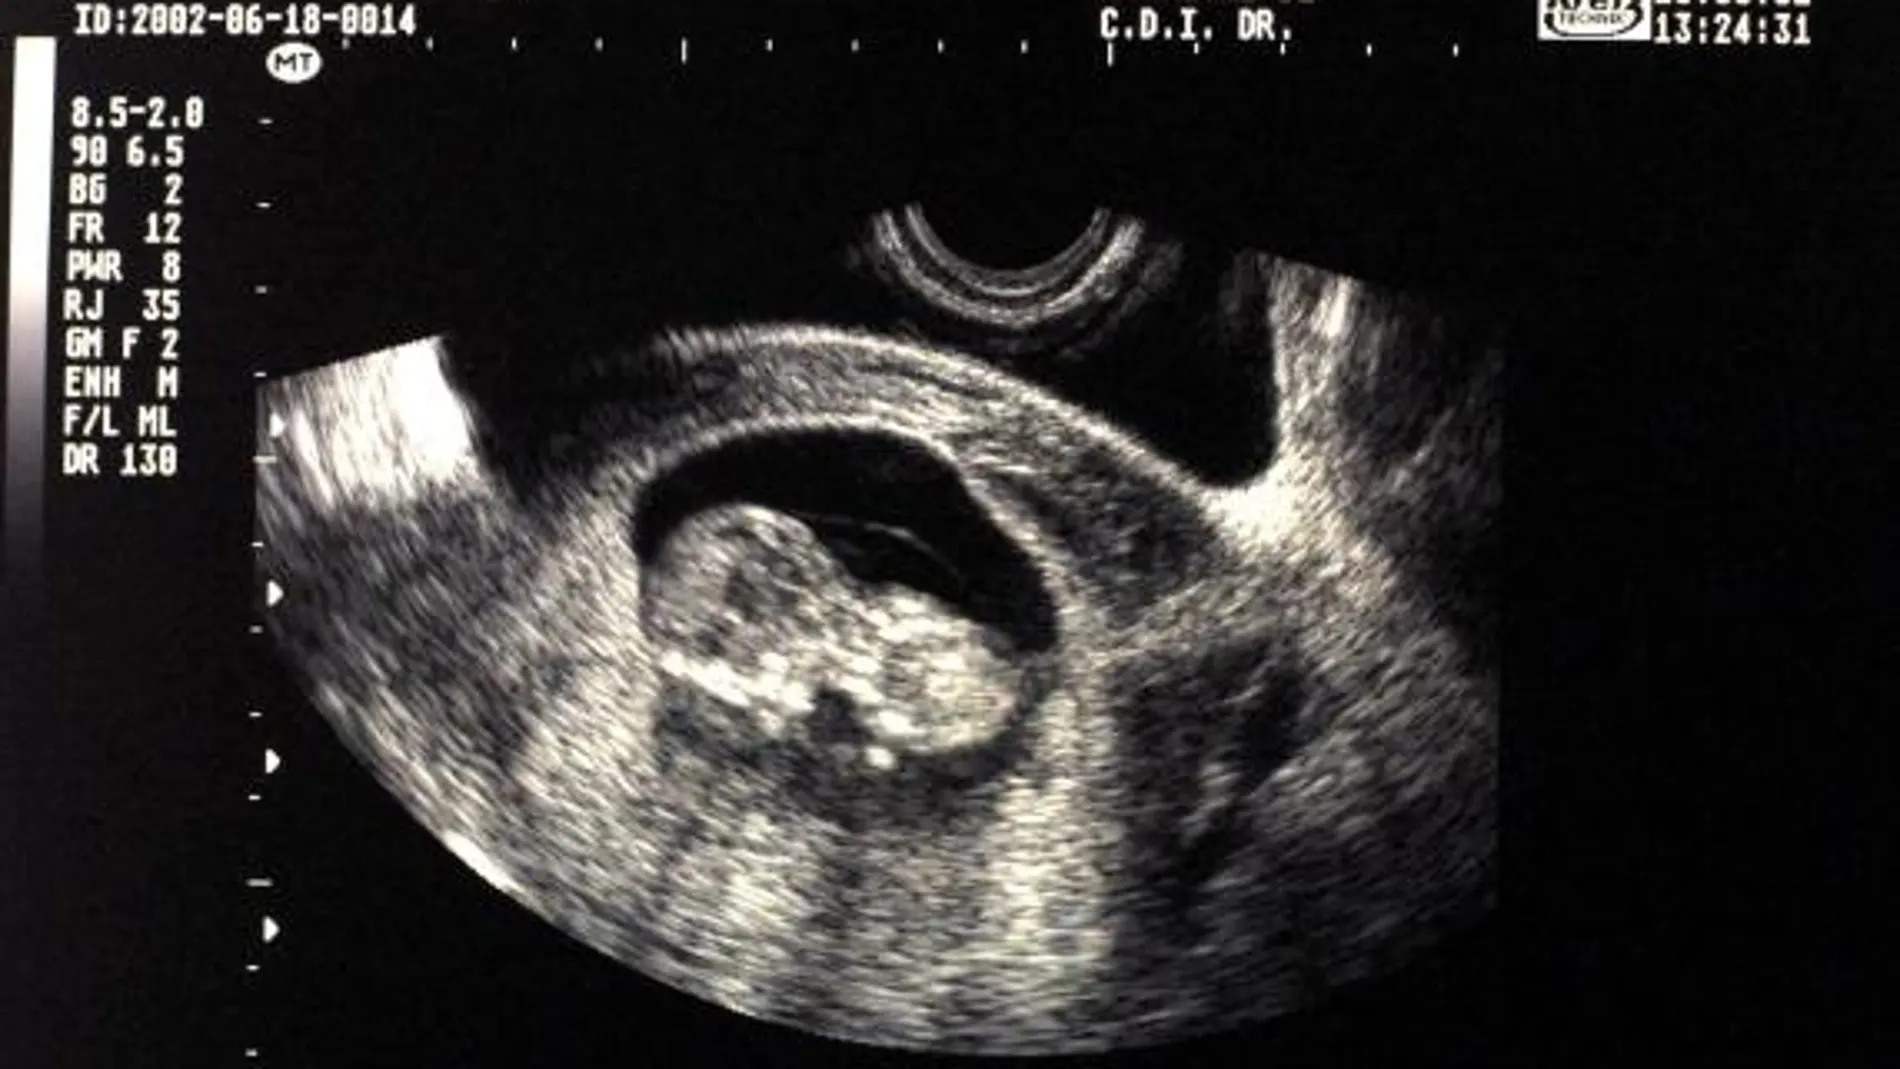

¿Cuántos abortos se realizan al año en Andalucía?

En Andalucía se practicaron en 2021 un total de 17.487 interrupciones voluntarias del embarazo (IVE), de las que 17.463 se realizaron en centros extrahospitalarios (17.462 privados y uno público) y 24 en hospitales (15 privados y 9 públicos).

Según los datos facilitados este martes por el Ministerio de Sanidad, 15.944 de las intervenciones se produjeron a petición de la mujer, mientras en 935 casos el motivo fue el grave riesgo para la vida o la salud de la embarazada, en 578 el riesgo de graves anomalías en el feto y en 30 la existencia de anomalías fetales incompatibles con la vida o enfermedad extremadamente grave e incurable.

En 12.843 casos el embarazo se encontraba por debajo de las 8 semanas de gestación, entre las 9 y las 14 en 3.758 casos; de 15 a 22 semanas en 865 y 21 en la semana 23 o posteriores.